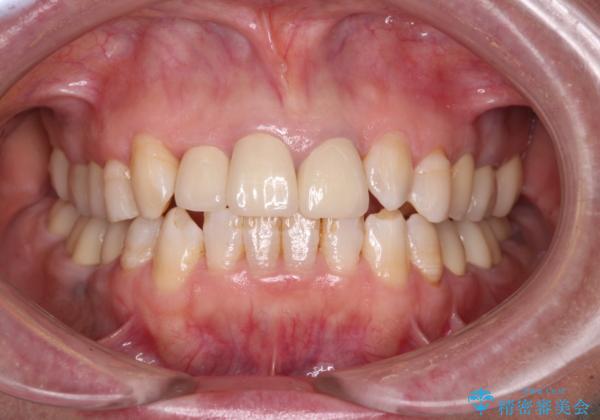

歯冠長延長術を行ったことで、自然な形態かつ清掃性の高いセラミッククラウンを装着することができました。

全顎的に治療を行ったため、治療期間も費用も負担は大きくなりましたが、統一感のある仕上がりとなりました。